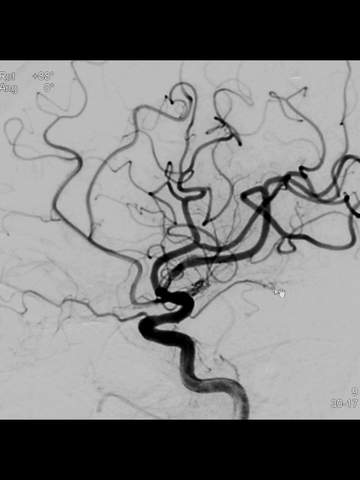

海绵窦段中间管回血通畅后,造影示右ICA和MCA完全再通,前向血流良好。

放大造影示:右MCA下干近端痉挛狭窄;等待5分钟后造影见痉挛改善。

后续造影见右MCA下干痉挛明显改善;但右ACA显影不佳。

后将导管头置于左CCA开口造影:右ACA主要由左A1经前交通供血。